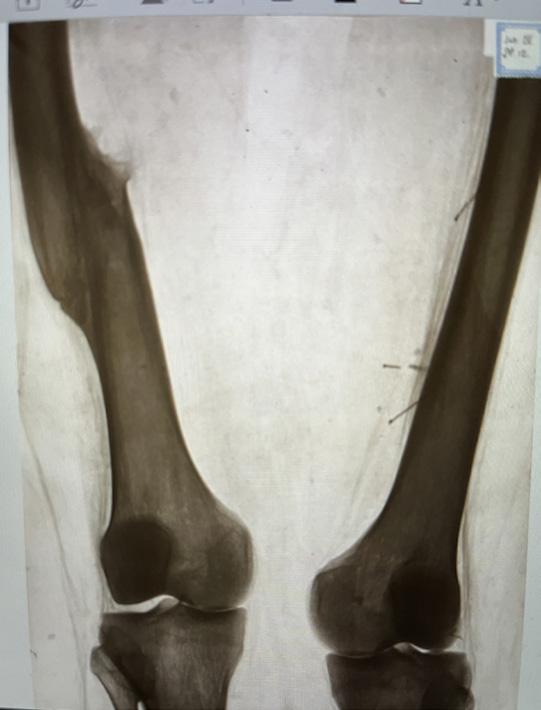

Bild 3. En 45-årig patient med smärtsymtom i mediala kompartment. T2-mappning av brosk i knäet visade förtjockning och förändrad brosksignal (pilar) som är förenligt med skada/degeneration. Dock är degeneration av brosk i främre delen (böjd pil) också synlig, vilket ännu inte syns på konventionella sekvenser. Denna undersökning möjliggör bedömning av tidiga artrosförändringar innan de blir synliga på konventionella sekvenser.